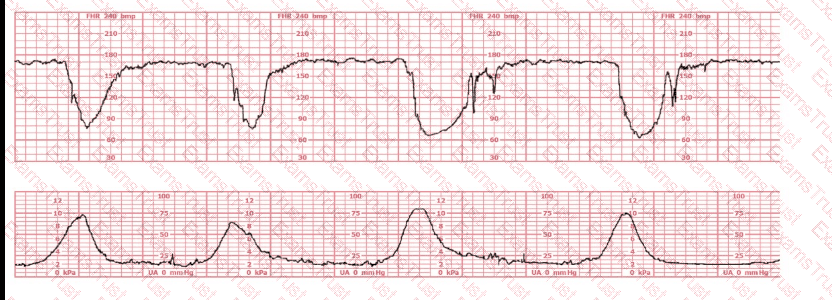

A woman has been 5 cm dilated for the past 3 hours. The tracing shown has developed over the last 30 minutes. The best initial course of action is to:

This fetal heart rate tracing is of a woman in labor with dichorionic-diamniotic twins at 36-weeks gestation, 4 cm dilated. She is on oxygen via face mask. Based on the fetal heart rate tracing, what is the most appropriate action?

The black pattern represents the heart rate pattern for Baby A. The blue pattern represents the heart rate pattern for Baby B. A possible etiology of the baseline fetal heart rate of Baby A is:

A patient at 41 weeks gestation is being induced. She has progressed slowly and is now at 6 cm, 90% effaced, –1 station. She has the fetal heart tracing shown despite repositioning. The next step in the management of this patient should be to: